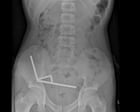

Un ragazzo di 13 anni in Nuova Zelanda ha ingerito fino a 100 potenti magneti acquistati online, costringendo i chirurghi a rimuovere tessuto dalle sue intestina, hanno dichiarato i medici venerdì.

Dopo aver sofferto per quattro giorni di dolori addominali, il teenager anonimo è stato portato all’ospedale di Tauranga sull’Isola del Nord. “Ha ammesso di aver ingerito circa 80-100 magneti ad alta potenza (neodimio) di dimensioni 5x2mm circa una settimana prima”, ha detto un rapporto dei medici dell’ospedale nella rivista medica neozelandese.